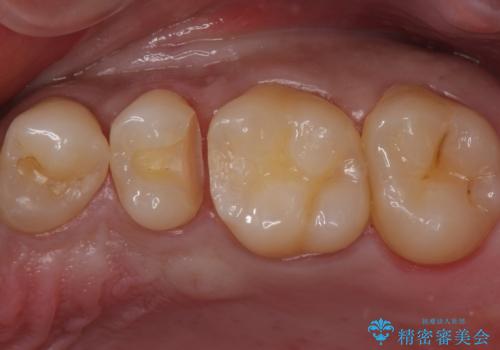

歯と歯の間の虫歯 セラミックインレーでの治療

- 検査の結果虫歯が見つかった患者様です。

レントゲン画像と視診から詰め物で対応可能と判断したためインレーでの修復をしていきます。

- 左上5 セラミックインレー/77,000円費用は治療当時の料金となります

適合の良いインレーは段差がない上にセラミックは汚れがつきにくい材料であるため今後の虫歯発生リスクを抑えることに繋がります。